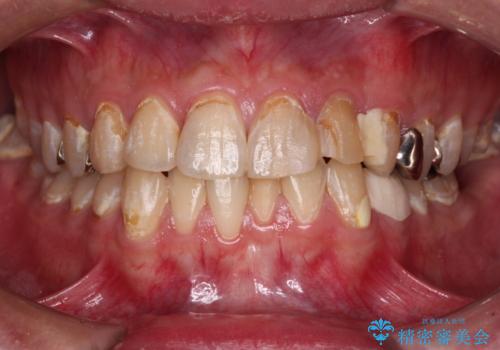

- むし歯の影響で、前歯を見せることが恥ずかしいとのことで来院された患者様です。

全顎的にむし歯が多く、治療が必要な歯はたくさんありましたが、まずは非常に目立つ前歯から処置を行うこととしました。

むし歯は歯肉内にまで進行していると外科処置が必要となりますが、ギリギリの位置でとどまっていたため、速やかにオールセラミッククラウンにて補綴治療することとしました。